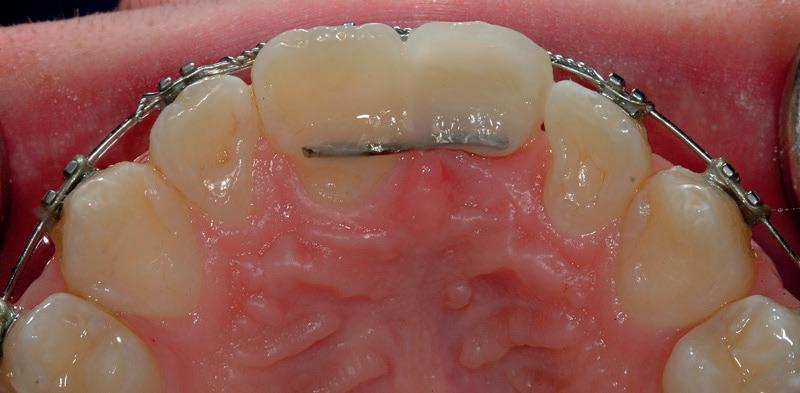

RECONFIGURAREA suportului osos implantar. În cazul prezentat, după ani de terapie ortodontică incorect executată, dezvoltarea dentară a pacientului a complicat obținerea unui zâmbet estetic. S-a reanalizat și s-a optat pentru abordare interdisciplinară care cuprinde chirurgia parodontală, un al doilea tratament

ortodontic și protetica pentru a oferi îngrijirea comprehensivă.